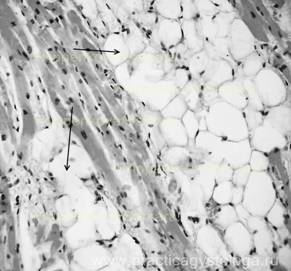

Рис. 7, 8. Очаги интерстициального липоматоза в миокарде. Окраска: гематоксилин-эозин. Увеличение х100 и х250.